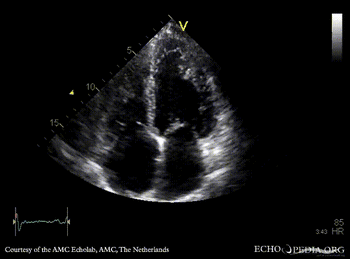

PLAX: dilated left ventricle, poor function, tenting of mitral valve PLAX with Color Doppler: severe mitral valve regurgitation